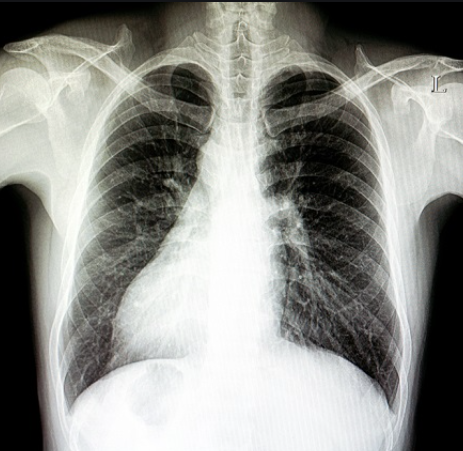

(i) X-ray images of the entire human body

1. An X-ray is a quick and painless procedure commonly used to produce images of the inside of the body. It’s a very effective way of looking at the bones and can be used to help detect a range of conditions.

2. X-rays can be used to examine most areas of the body. They’re mainly used to look at the bones and joints, although they’re sometimes used to detect problems affecting soft tissue, such as internal organs.

3. The X-ray machine, which looks like a tube containing a large light bulb, will be carefully aimed at the part of the body being examined by the radiographer.